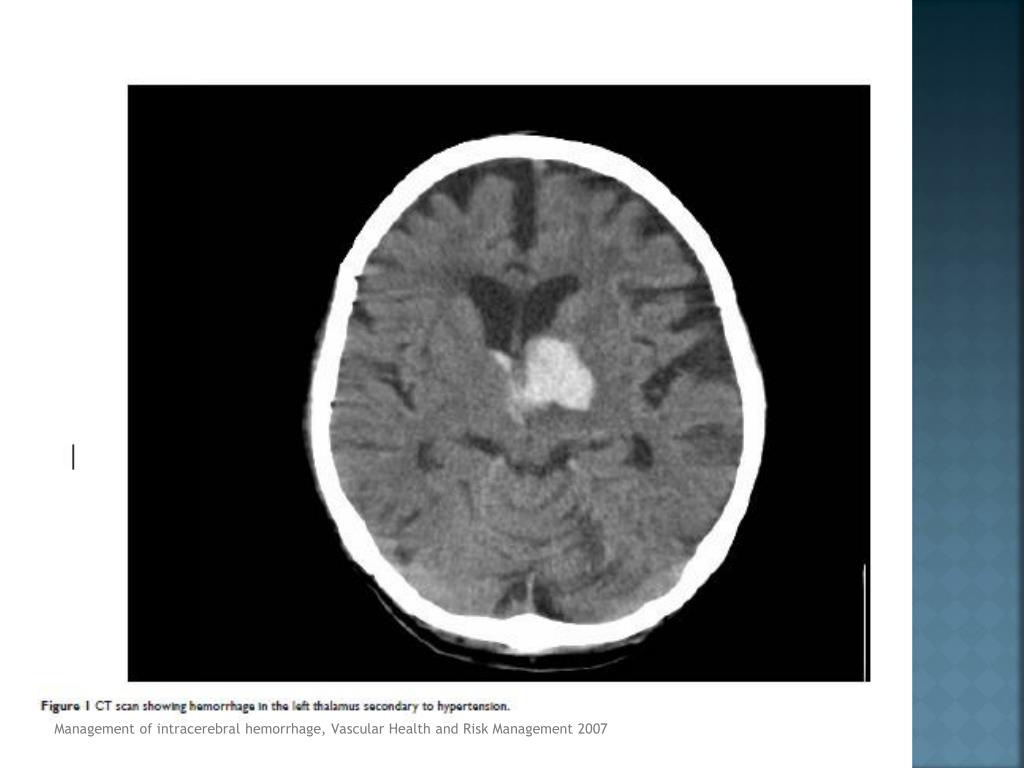

18. Tomografía axial computarizada (TAC) método dx. de elección (Clase 1A) • CT Angiography o TAC resalte de contraste • Expansión de hematoma (Clase IIB) • RMN (Clase 1A) • Hemorragia hiperaguda menor a 6 horas • Causa subyacente • Angiografía • Ptes. menores de 45 a • No riesgo de HIC primaria o hipertensiva • HSA • Estructuras vasculares prominentes • Hemorragia perisilviana o interhemisferica Management of intracerebralhemorrhage, Vascular Health and Risk Management 2007, Guidelinesforthe Management of SpontaneousIntracerebralHemorrhage, AHA/ASA 2010

19. Management of intracerebralhemorrhage, Vascular Health and Risk Management 2007

20. Management of intracerebralhemorrhage, Vascular Health and Risk Management 2007